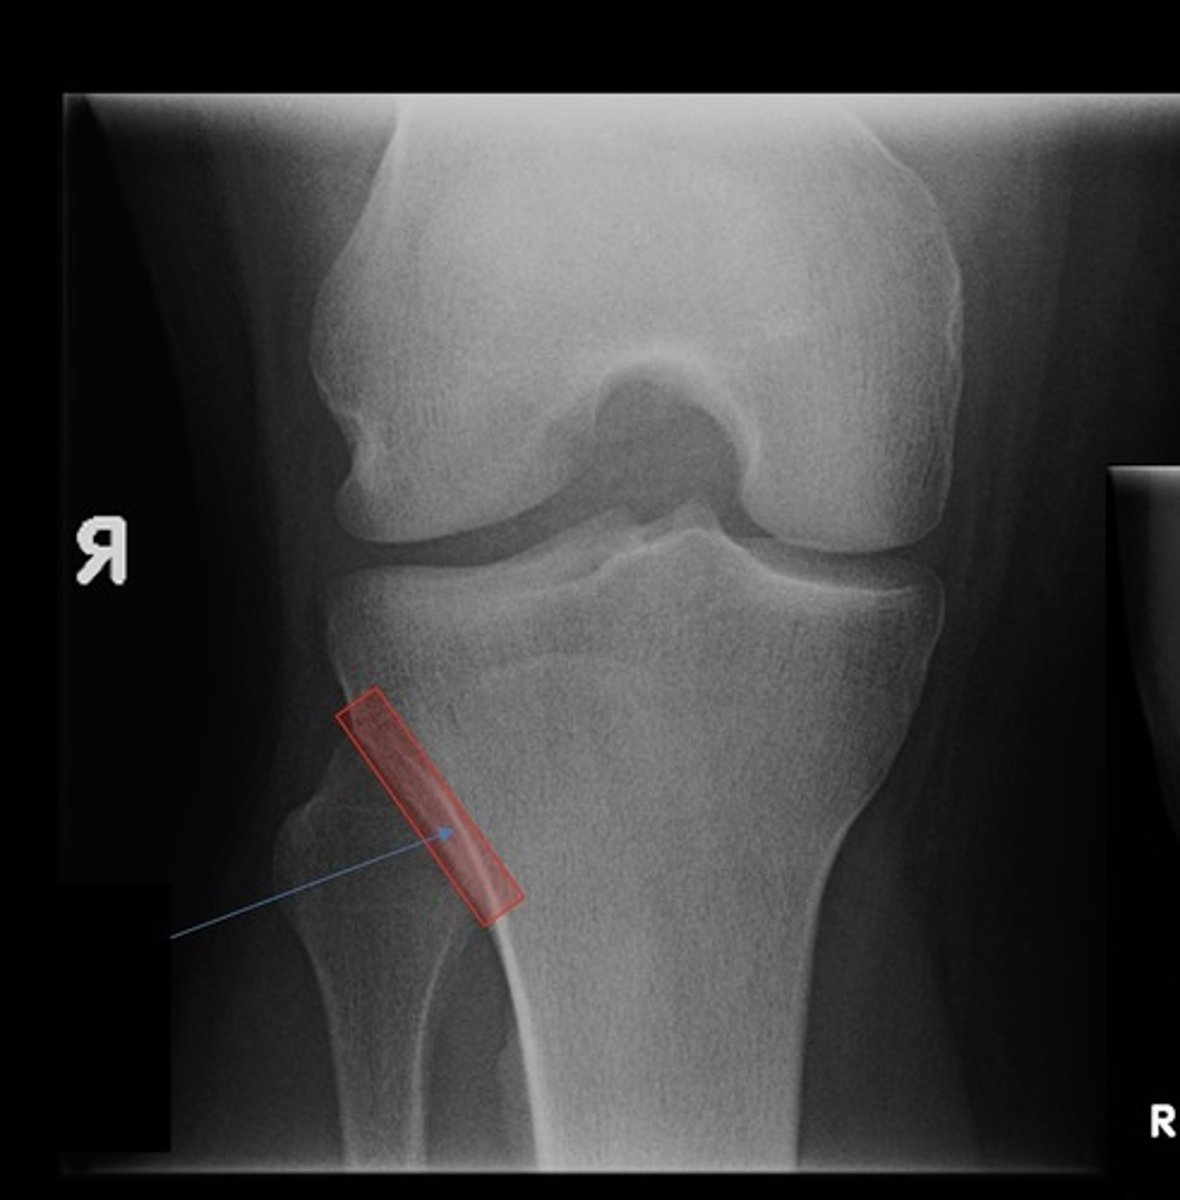

tibial tuberosity (lat)

fibular head (lat)

proximal tibiofibular joint